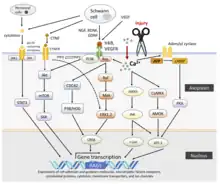

Neuron-intrinsic changes

Immediately following injury, neurons undergo a large number of transcriptional and proteomic changes which switch the cell from a mature, synaptically active neuron to a synaptically silent, growth state. This process is dependent on new transcription, as blocking the ability of cells to transcribe new mRNA severely impairs regeneration. A number of signaling pathways have been shown to be turned on by axon injury and help to enable long distance regeneration including BMP, TGFβ, and MAPKs. Similarly, a growing number of transcription factors also boost the regenerative capacity of peripheral neurons including ASCL1, ATF3, CREB1, HIF1α, JUN, KLF6, KLF7, MYC, SMAD1, SMAD2, SMAD3, SOX11, SRF, STAT3, TP53, and XBP1. Several of these can also boost the regenerative capacity of CNS neurons, making them potential therapeutic targets for treating spinal cord injury and stroke.[4]